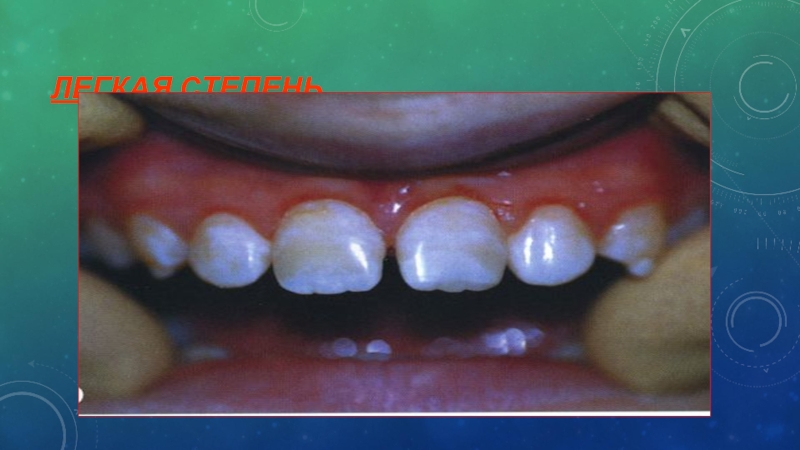

Слайд 40ЛЕГКАЯ СТЕПЕНЬ